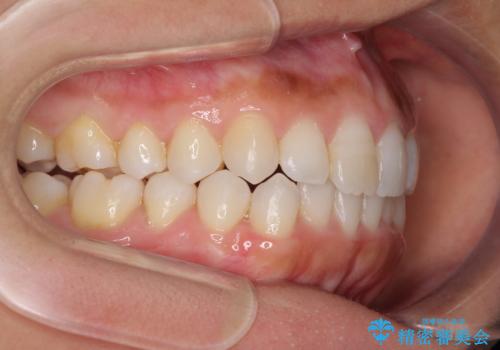

前歯の叢生を治したい インビザラインによる矯正治療

- 上下の前歯のデコボコと奥歯の反対咬合を気にして来院された患者様です。

インビザラインを用い、上下顎ともにIPR(歯と歯の間を削る)により叢生を改善することとしました。

奥歯の反対咬合は、骨格に由来するものであるため、改善できるところまで改善していくこととしました。

治療を長期化させたくないとのご要望があったので、左下の90度捻転した歯は、捻転した状態のゴールとしました。

反対咬合を改善したことで、歯ぎしりしたときの引っかかる感じがなくなり、奥歯への負担を大きく軽減することができました。